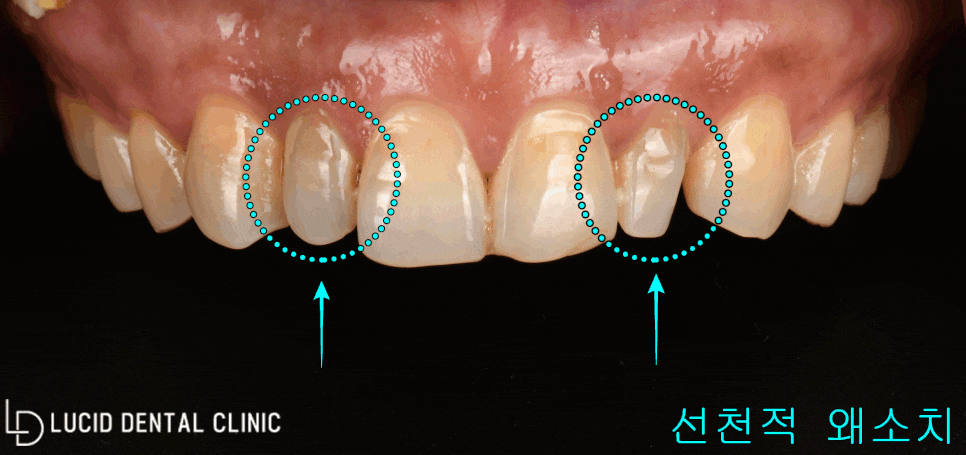

곧장 어금니끼리 편하게 교합한 다음,

정면에서 바라본 모습을 촬영해 봤는데요

위턱 앞니를 중점으로

- 좌, 우 크기 불일치

그리고

- 좌, 우 측절치 왜소치

이렇게 두 가지를 발견할 수 있었습니다.